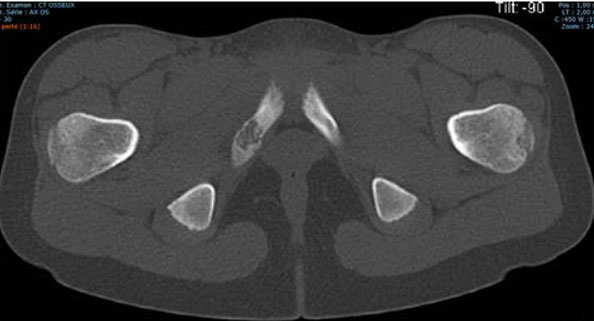

As observed in the Herneth study [3], pelvic magnetic resonance imaging (MRI) performed on a whole-body 1.5 T scanner (Avanto, Siemens Medical Systems, Erlangen, Germany) revealed hyperintense signal alteration of the bone marrow surrounding the right IPS on T2-weighted images, widening of the synchondrosis, and a hypointense band-line structure perpendicular to the pubic axis in the center of the IPS. Moderate hyperintense signals were also noted in the surrounding soft tissues (Figure 2). A computed tomography (CT) scan demonstrated focal enlargement of the right ischiopubic branch with central radiolucency and cortical thinning (Figure 3).

Improvement in symptoms was noted after one month of anti-inflammatory therapy and cessation of sports activities. A follow-up MRI after one month showed a significant decrease in perilesional edema, consistent with Macarini’s observations [4], confirming the non-tumoral nature of the condition and highlighting the importance of conservative management in such cases.

Figure 2: Pelvic MRI performed on a whole-body 1.5 T scanner (Avanto, Siemens Medical Systems, Erlangen, Germany) shows hyperintense signal alteration of the bone marrow surrounding the right ischiopubic synchondrosis on T2-weighted images, with widening of the synchondrosis and a hypointense band-line structure perpendicular to the pubic axis at the center of the IPS. Moderate hyperintense signal of the surrounding soft tissues is also visible.

Share Image: